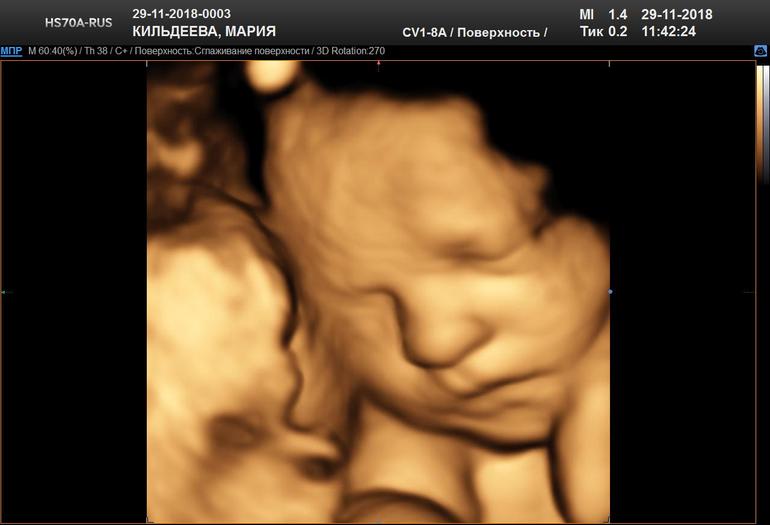

31 неделька и 3 дня,5d узи в Арт мед.

Сегодня съездили с мужем в медицинский центр на Красной пресне и сделали 5d УЗИ.Ну что я могу сказать,впечатления непередаваемые. У мужа с лица не сходила улыбка,это надо было видеть.😊

И сегодня нам уже на 100 процентов подтвердили девочку.Такая крошка милая,и пальчик на ноге сосала и улыбалась и ручками моську прятала.Дали диск с видео с комментариями врача,распечатали 10 фотографий,дали заключение и скинули цветные фото в программу Hello mom на телефон. Рекомендую Варламову Ольгу Леонидовну,чудесный доктор. Ну а теперь прошу ,знакомьтесь .Наша Елизавета Алексеевна.